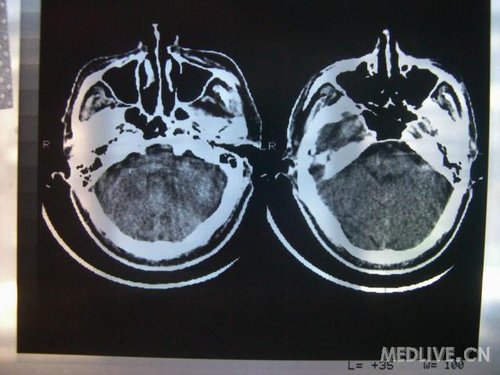

病人男性 73岁 市民 以“幻听、幻视两天,言语含糊、精神错乱一天”入院。

两天前无诱因出现幻听、幻视,描素眼前有彩色的圆圈,听见有人说话(但说什么不详),一天前出现胡言乱语,言语含糊,精神错乱,问话不答,行走略有不稳,来我院就诊,门诊头CT检查:(下面有片)入院后查体不合作,表情淡漠,问话不答,大致检查了一下,颅神经未见明显异常,颈软,右手活动似忽略差。其他检查不配合。脑电图:广泛轻-中度异常。

既往史:半年前曾患“右侧脑梗塞”但无明显后遗症,生活能自理,无高血压、糖尿病、心脏病史。

先传半年前的片子:

此次入院时的片子: